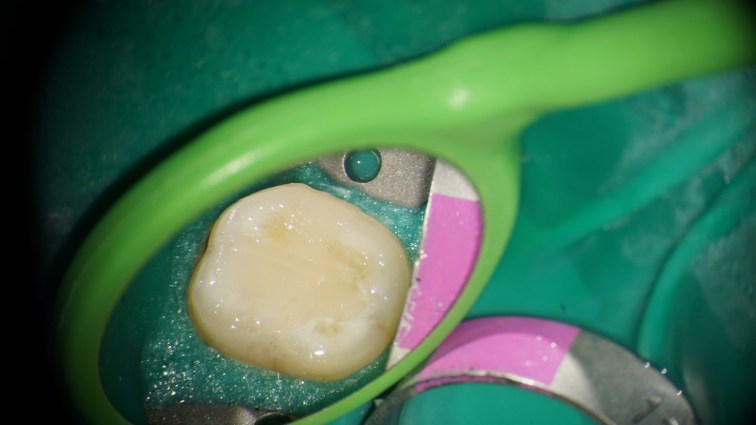

This is a “garden variety” endo. The best time to refer a case to an endodontist with a microscope is before the pulp has been touched. That way, the endodontist can control how much of tooth structure is removed to complete the endo. In this case, I had to chase all the cracks before restoring